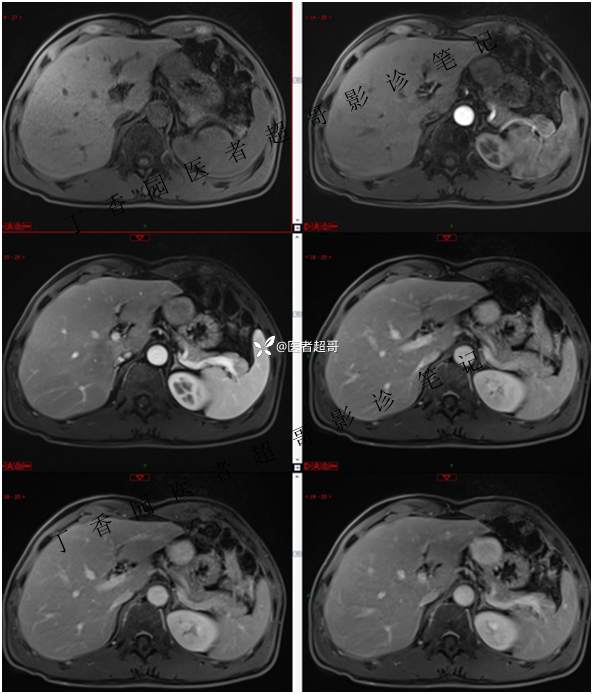

肝胃间隙肿瘤,间质瘤?平滑肌瘤?还是鞘瘤?有结果,请分析!

主 诉:查体发现肝占位3天。

现病史:患者于3天前查体行肝胆脾胰肾彩超示肝内实性占位,无恶心、呕吐,无发热、寒战,无腹胀、腹泻,进一步于医院行上腹部CT增强示:肝胃交界处肿块。未行特殊治疗。今患者为求进一步治疗,来我院就诊,门诊以“肝占位性病变”收入院。患者自发病以来,神志清,精神可,饮食睡眠可,二便可,体重近期未见明显变化。